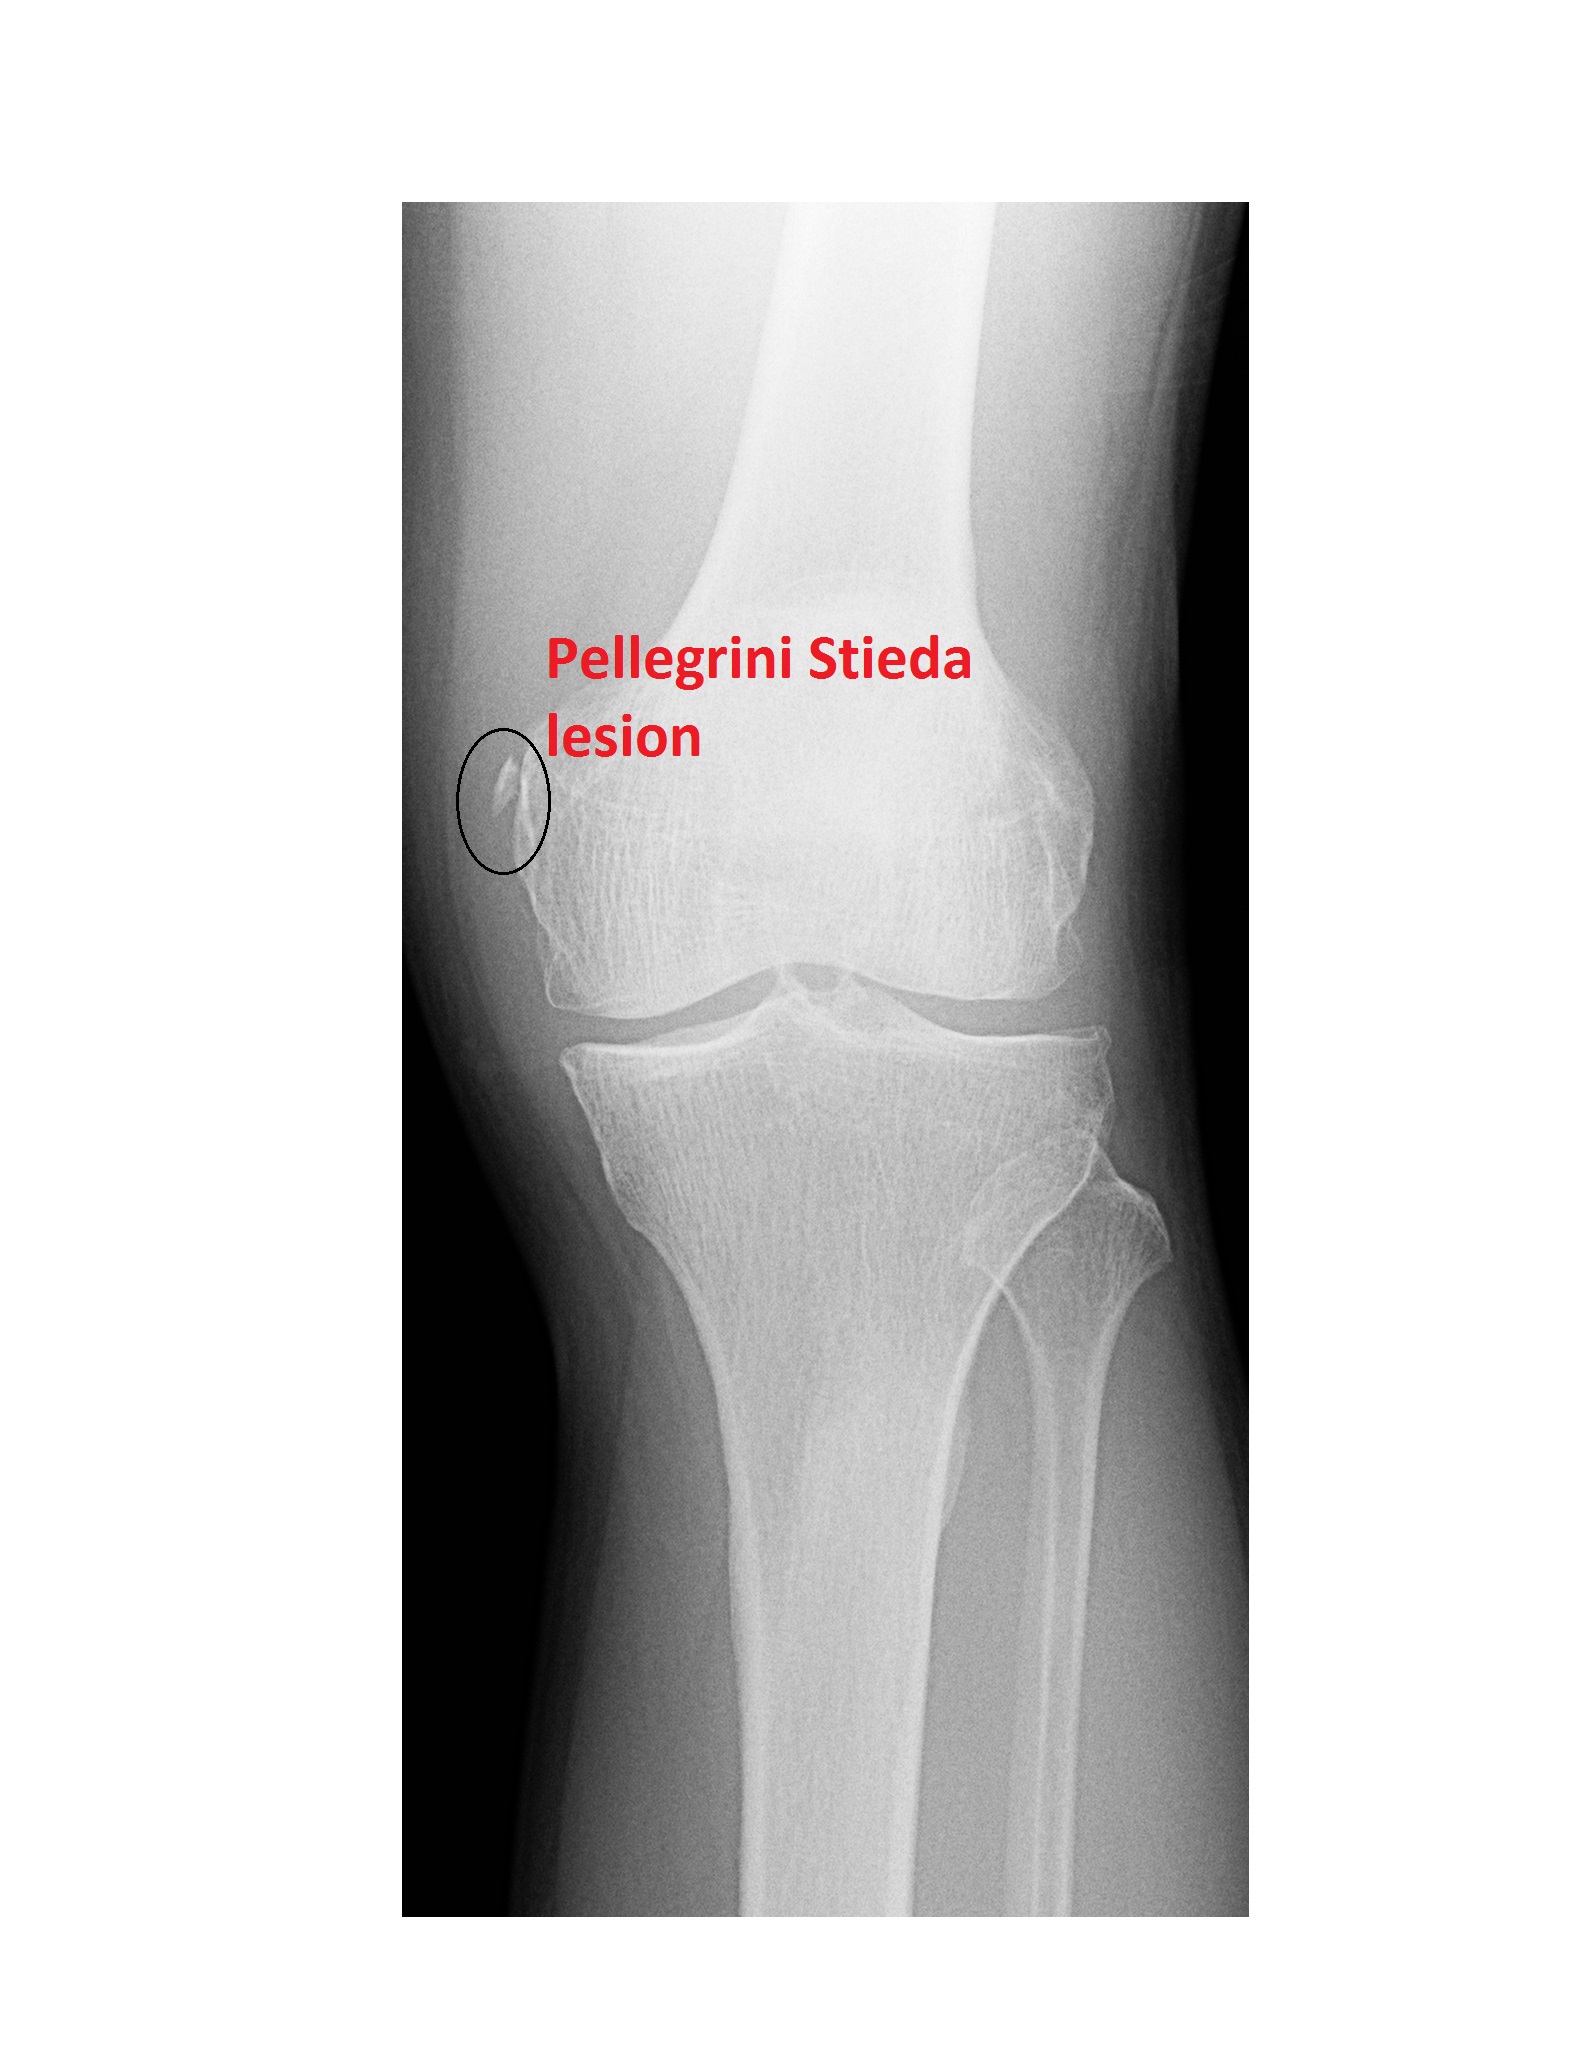

Discover how an MRI wrist joint scan provides detailed imaging to accurately diagnose complex injuries, ligament tears, and chronic pain. Learn why this advanced medical imaging procedure is essential for identifying bone, tendon, and soft tissue conditions, helping your doctor create an effective treatment plan for improved wrist health and faster recovery.

Read full article: Mri Wrist Joint